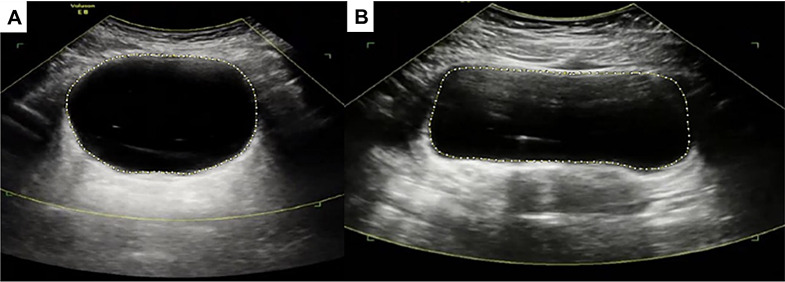

Recent findings: Bladder Near-Infrared Spectroscopy (NIRS) has been used to non-invasively identify bladder outlet obstruction, detrusor overactivity, and other forms of voiding dysfunction, but motion artifact has been a limiting factor preventing widespread adaptation. However, newer NIRS units employ accelerometers which enable isolation and splicing of motion and on-going studies show renewed promise for bladder NIRS. Ultrasound has been successfully used to evaluate bladder outlet obstruction and other forms of LUT. Techniques including m-mode evaluation of micromotion, as well as the assessment of bladder wall thickness, bladder weight, shape/circularity, vibrometry, and elastography have been explored. Dynamic bladder functional magnetic resonance imaging (fMRI) is the newest bladder imaging technology on the horizon and provides a novel method to assess bladder function alongside real-time high-resolution 3D anatomic images.